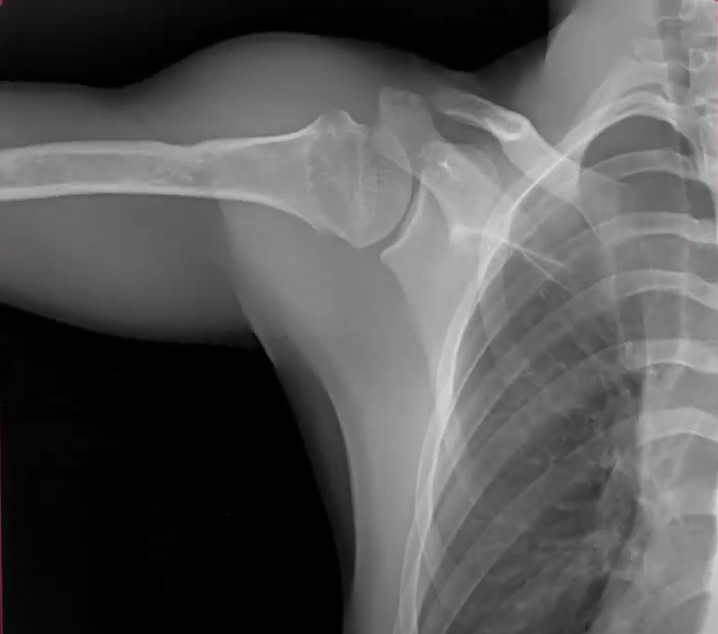

Xray Shoulder joint shoulder front view for diagnosis fracture of Shoulder X-Ray Definition The stronger the magnet, the higher the intrinsic. Shoulder radiographs are often the only imaging exam necessary for the evaluation of acute shoulder trauma, calcific tendonitis,. Mri is best for evaluating soft tissue structures and evaluating bone contusions or trabelcular microfractures. The grashey view involves angling the beam laterally or rotating the patient posteriorly(2). Shoulder X-Ray Definition.